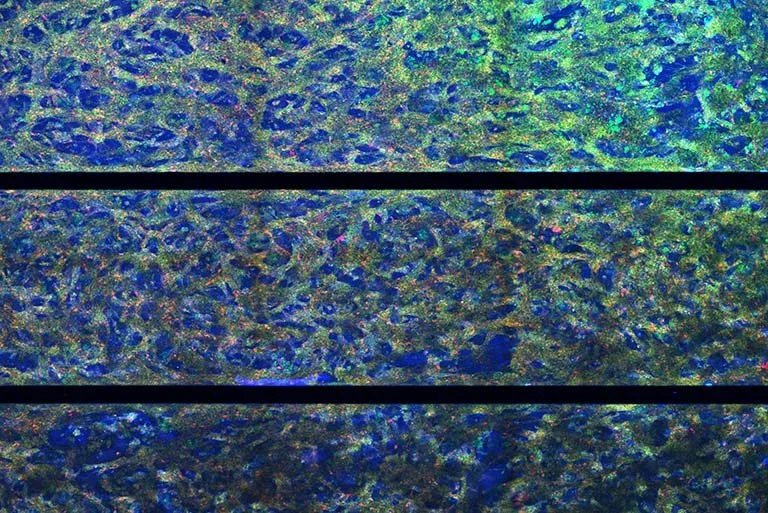

The research at the Bose Lab lies at the interface of biomaterial science, cellular engineering, and drug delivery with the aim of creating next-generation cell-based therapies for a wide range of human diseases. The lab combines multiscale device fabrication, material chemistry, and cell engineering principles to develop platform technologies capable of delivering precise doses of drugs (biologics) at the right location in the body at the right time. These platforms have applications in treating chronic diseases such as diabetes and liver failure, immune engineering applications in cancer and autoimmunity, and regenerative medicine.